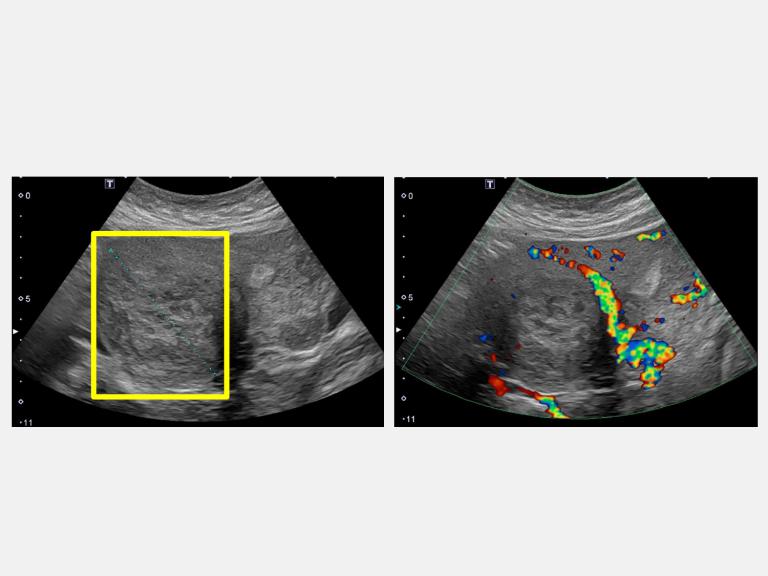

▲超音波顯示病人下腹部悶痛合併壓迫症狀,有7公分肌瘤(左圖方框處)。(圖╱仁愛長庚醫院提供)

45歲的魏女士因為近半年來出現下腹部悶痛,所以到仁愛長庚合作聯盟醫院(大里仁愛醫院)婦產科林玉珊醫師門診求診,檢查後發現有下腹部悶痛合併壓迫症狀,竟然有7公分的肌瘤。經採用達文西機械手臂系統結合經陰道自然孔手術,於術後一週後即返家休養。由於手術並未在腹部留下傷口,讓魏女士感到非常驚訝,林玉珊醫師表示,傷口只是藏在看不到的地方,這不只是手術傷口變小,更代表病人能更快回到自己的生活與角色中。